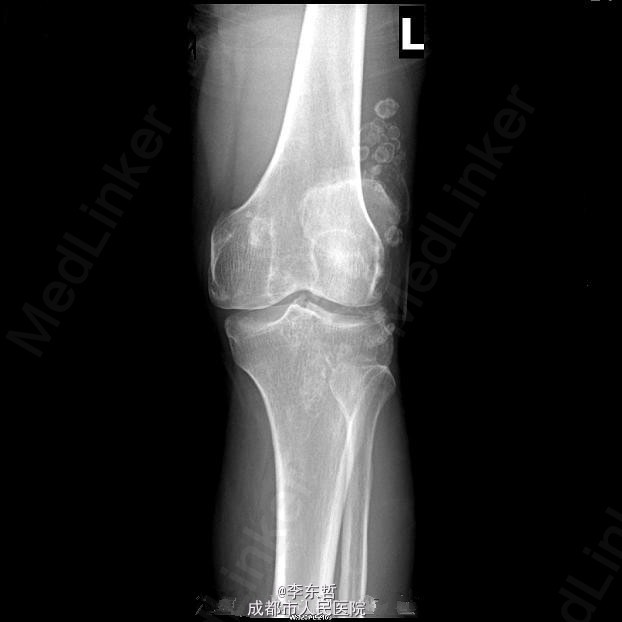

滑膜骨软骨瘤病

患者男性,43岁,自述关节疼痛、肿胀和活动受限数年,偶可触及游离体,常出现关节交锁;